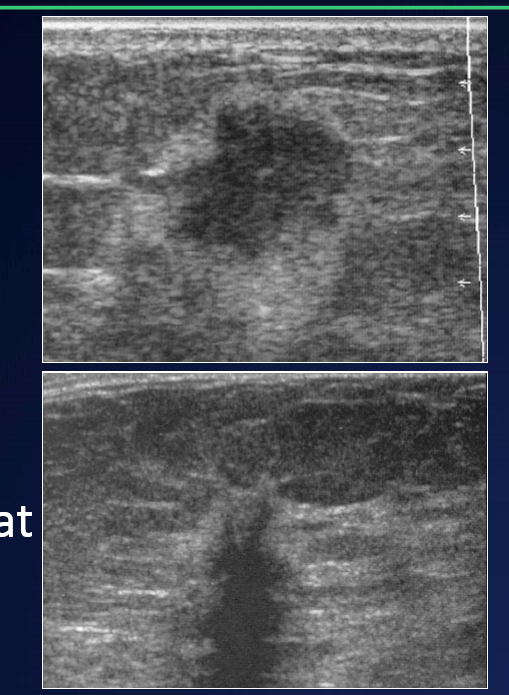

Q

Describe the appearance of malignant solid breast lesions on US

A

• Poorly Circumscribed - bad borders

• Hypoechoic

• Heterogeneous

• “taller than wide”

• Spiculate

• Oedema/peritumoral fat